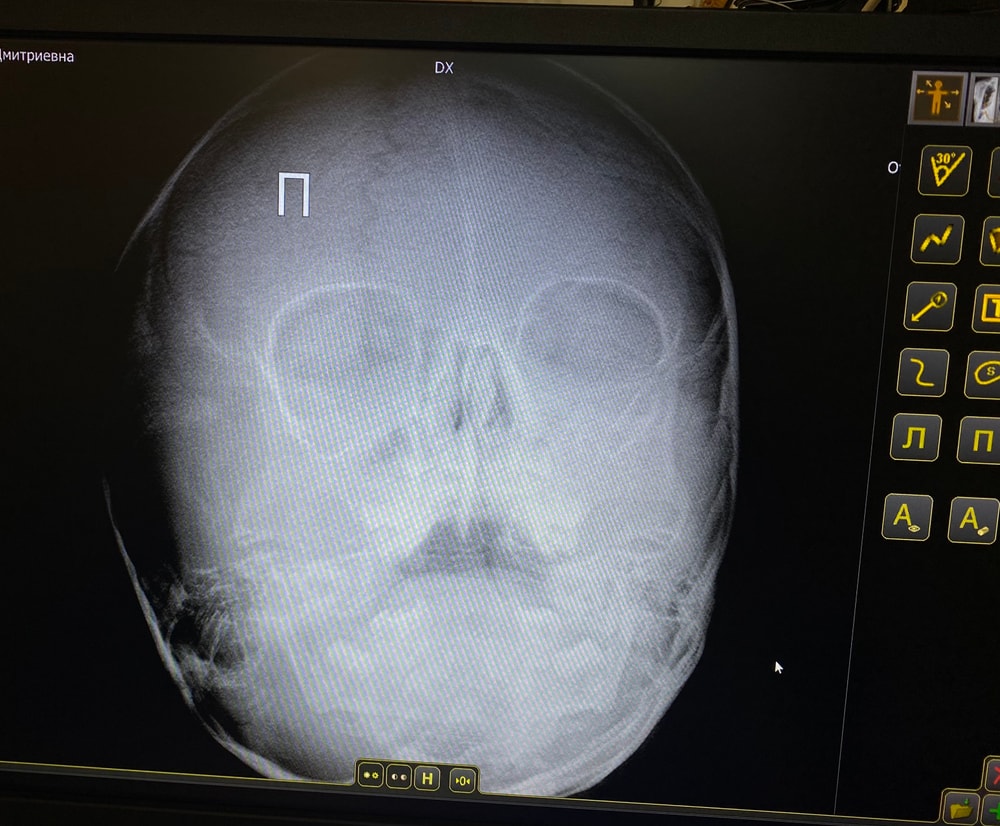

Аденоиды снимок

Анализы, УЗИ, РентгенДевочки,помогите , пожалуйста. Может быть кто то понимает по снимку. На этом снимке видео аденоиды?и если да,то какой степени?

к врачу мы записаны через месяц,очень плотная запись к хорошему платному врачу. На предыдущем приеме не удалось сделать снимок,посмотрели длинной палочкой,не знаю название. Поставили 2-3 степень. Мы в нашей поликлиники сделали снимок чтобы было с чем сравнить для следующего раза. Но я вот не понимаю,подходит ли такой снимок,так как у врача снимки были (других пациентов)боком.

Аденоиды давно уже анализирую эндосокпически только. Снимок не даст четкой картины и про степень и про направление разрастания. Покажет только, что увеличины, возможно предположить только степень.

Анна Нартова, а нам оперирующий врач сказал обратное, что видно лучше на снимке (но не этом конечно,это мы уже не у него делали) эндоскопически нам проверяли. Но врач сказал что лучше снимок

Екатерина , какой у вас "старорежимный" врач. Сколько ЛОРов в своё время прошли с аденоидами и операцией - только эндоскопия.